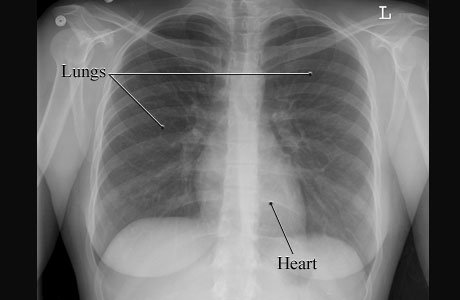

This is a picture of a normal chest X-ray of a woman showing the air-filled spaces of the lungs and the more solid gray shape of the heart. The lungs and heart are normal in size and shape.